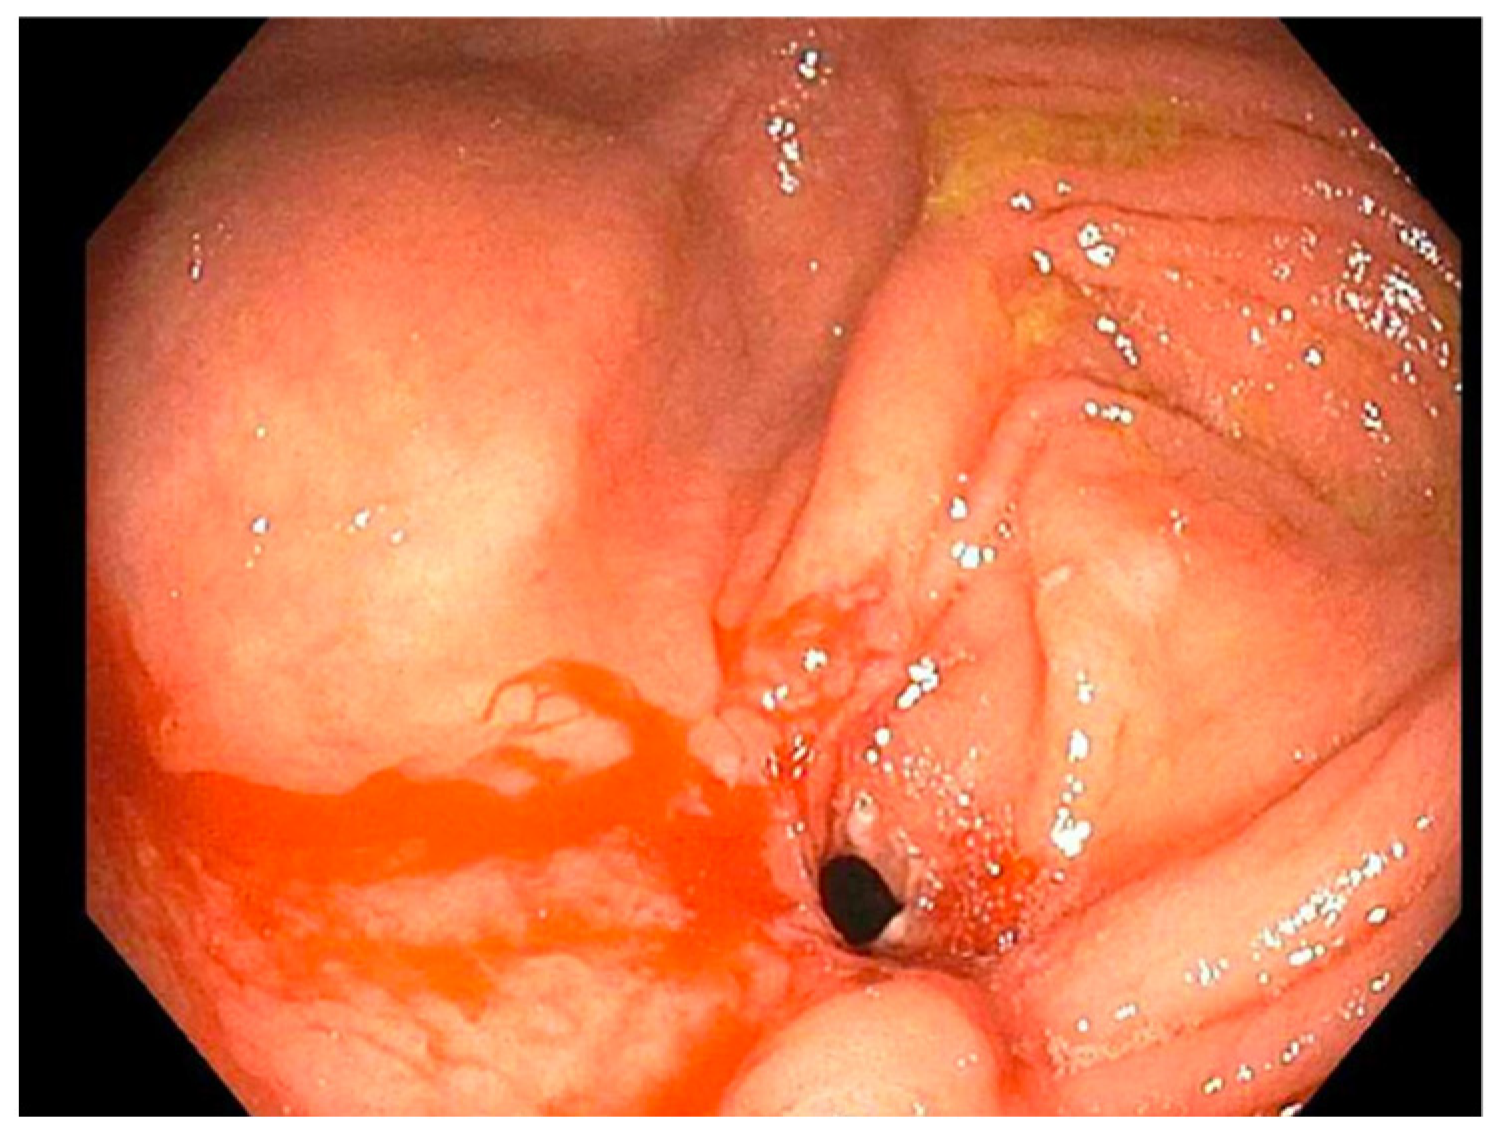

| 1 | (2019: Remicade 10 mg) (2019: Humira 40 mg) (2020: Humira 80 mg subcutaneous) | November 2019, dilated (b) TI from (12 to 18 mm) (a) TI stricture dilated to (16.5 mm) | November 2020, dilated TI to (20 mm) | March 2023, laparoscopic assisted ileocecectomy |

| 2 | (2019: prednisone 40 mg) (2019: Remicade 5 mg) (Remicade 10 mg) | September 2019, ICV dilated from (8 to 11 mm) | December 2020 and August 2021 ICV dilated from (9 to 18 mm) then (12 to 18 mm) | June 2022, ICV dilated from (13.5 to 20 mm) |

| 3 | (2019: prednisone 20 mg BID w/mesalamine 500 mg TID) (2020: 6-MP 50 mg) (2021: Humira 40 mg/MTX 25 mg) | February 2021, PAC dilated from (7 to 15 mm) | August 2021, PAC dilated from (15 to 20 mm) | August 2022, mucosal narrowing stretched to 20 mm without noted renting |

| 4 | (2021: Humira 40 mg every other week/steroid 40 mg daily, escalated to Humira 40 mg weekly) (2022: MTX 25 mg) | September 2022, dilation of the ICV from (4 to 13.5 mm) (food bezoar noted) | November 2022, ICV dilated from (8 to 15 mm) | December 2022, ICV dilated (12 to 15 mm) |